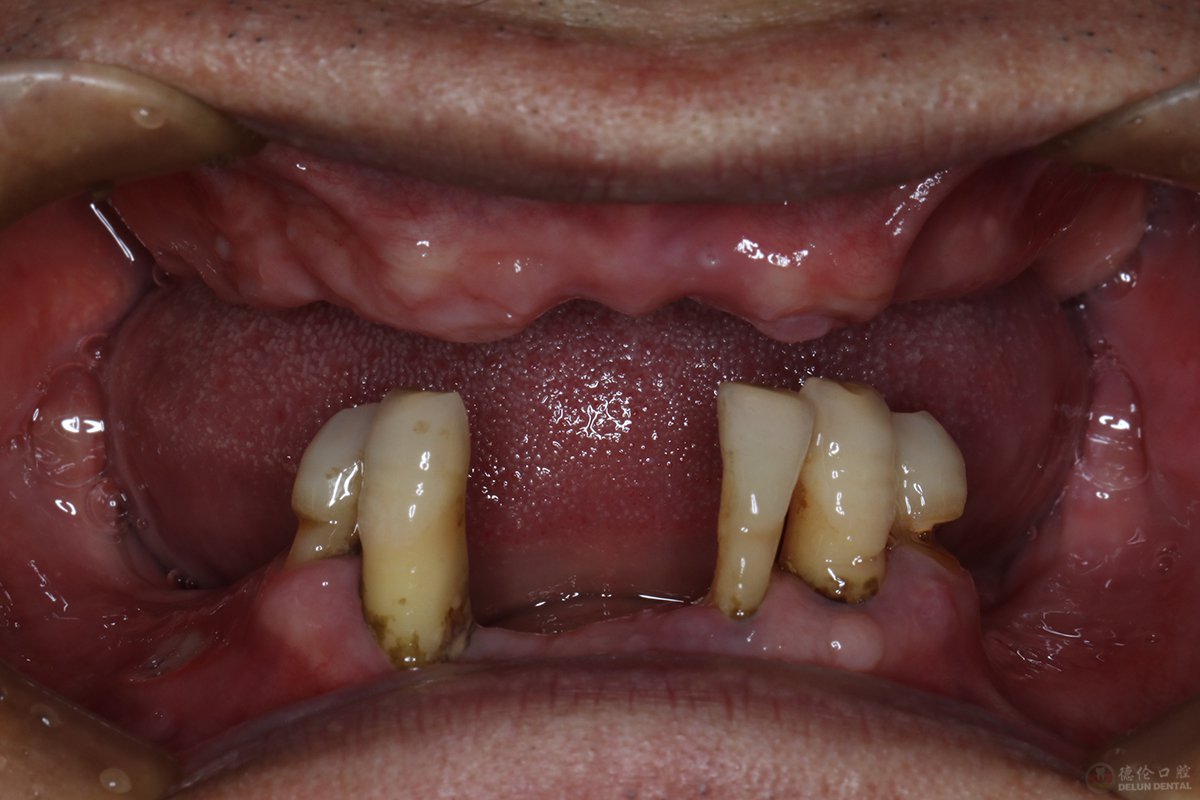

牙齿症状:上颌牙全部缺失、下颌牙缺失多颗(仅剩4颗)

直到2017年,苏先生的牙齿已经到了上半口牙全部缺失、下半口牙仅剩4、5颗的地步,多年来,活动假牙不适的问题依然困扰着他,然而却找不到好的方法。没想到当年轻易拔牙之举、平时口腔意识薄弱、多年戴活动假牙等这些行为竟然会导致牙齿沦为这般模样。